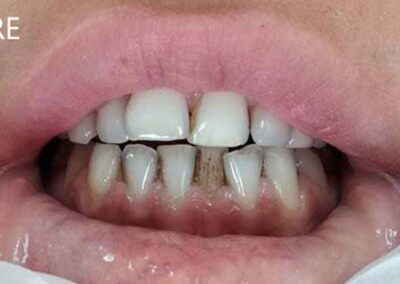

Slučaj 2

Pacijent je bio nezadovoljan estetikom svojih zuba, bojom i njihovim nepravilnim položajem. Sa obe strane zubnog niza nedostajale su četvorke.

Svakom pacijentu izlažemo sve opcije terapije. Nakon razgovora, pacijent se opredelio za protetsku terapiju metalokeramičkim mostom, nije bio zainteresovan za ortodontsku.

Urađen je metalokeramički most poštujući morfologiju svih zuba u frontu, uz maksimalnu gracilnost incizalnih ivica na sekutićima, što je pojačalo zadovoljavajući estetski efekat.